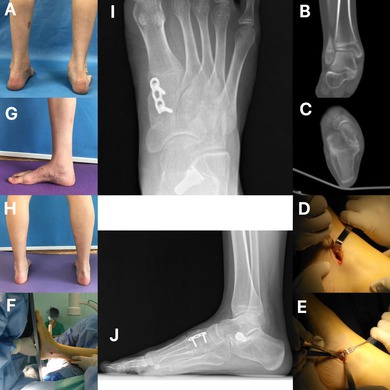

Objective: The treatment of talocalcaneal coalition (TCC) with pes planus deformity in adolescent patients still presents challenges. With the pes planus deformity untreated, the final clinical outcome would be compromised. Therefore, simultaneous correction of pes planus deformity seems to be of great importance. This study aimed to retrospectively evaluate the clinical efficacy of coalition resection combined with extra-osseous talotarsal stabilization (EOTTS) treatment for adolescent TCC with pes planus deformity.

Methods: Data was reviewed for patients of TCC and pes planus deformity treated by coalition resection and EOTTS from January 2018 to January 2024. Meary's angle and talar-1st metatarsal angle (T1MA) were measured to assess the alignment improvement (paired sample t-test). Visual analog scale (VAS) for pain (Wilcoxon signed rank test) and American Orthopedic Foot & Ankle Society ankle-hindfoot score (AOFAS-AHS) (paired sample t-test) were evaluated for the overall clinical outcomes. Time to return to sports activity and complications were also recorded.

Results: No early wound or soft tissue complications occurred. At 1-year follow-up, Meary's angle and T1MA improved from 13.4° ± 5.2° to 5.1° ± 3.4°, and from 14.7° ± 3.7° to 6.4° ± 2.5°, respectively. The median VAS score decreased from 5 to 0, while the AOFAS-AHS increased from 51.1 ± 8.9 to 90.1 ± 9.3 (all p < 0.05). Fifteen patients returned to sports at a median of 3 months (range: 2-4 months). One patient experienced sinus tarsi pain, which was resolved after implant removal at 14th month postoperatively.

Conclusion: Simultaneous coalition resection and EOTTS for adolescent TCC with pes planus deformity achieves satisfactory clinical outcomes with minimal complications.